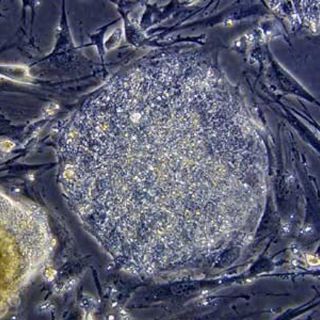

WASHINGTON, ESTADOS UNIDOS (21/JUL/2010).- Un grupo de investigadores alemanes introdujo diminutos andamios plásticos con células madre, modificadas por ingeniería genética, que redujeron los daños en el corazón de ratas que habían sufrido ataques cardiacos, según un informe presentado hoy.

Los investigadores seleccionaron cinco grupos de 10 ratas cada uno y les implantaron minúsculos andamios de poliuretano sembrados con células madre sobre las que se aplicaron diferentes modificaciones genéticas.